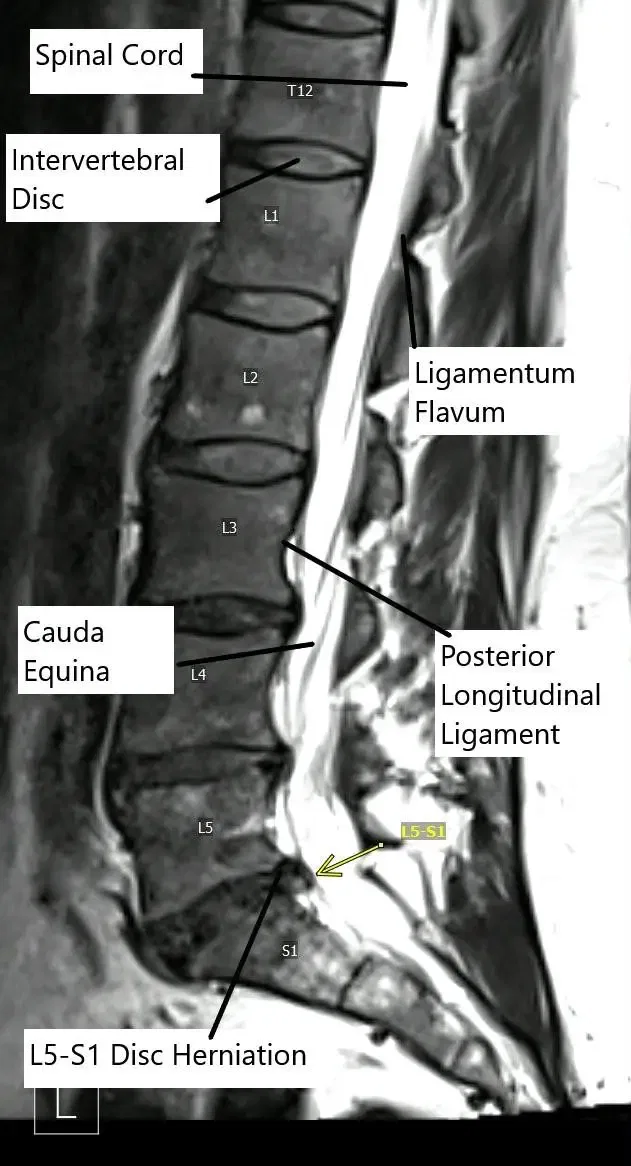

Sagittal section of the lumbar MRI showing L5-S1 disc herniation.